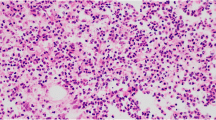

Our study aims to evaluate the potential of a deep learning (DL) algorithm for differentiating the signal intensity of bone marrow between osteomyelitis (OM), Charcot neuropathic osteoarthropathy (CNO), and trauma (TR). The local ethics committee approved this retrospective study. From 148 patients, segmentation resulted in 679 labeled regions for T1-weighted images (comprising 151 CNO, 257 OM, and 271 TR) and 714 labeled regions for T2-weighted images (consisting of 160 CNO, 272 OM, and 282 TR). We employed both multi-class classification (MCC) and binary-class classification (BCC) approaches to compare the classification outcomes of CNO, TR, and OM. The ResNet-50 and the EfficientNet-b0 accuracy values were computed at 96.2% and 97.1%, respectively, for T1-weighted images. Additionally, accuracy values for ResNet-50 and the EfficientNet-b0 were determined at 95.6% and 96.8%, respectively, for T2-weighted images. Also, according to BCC for CNO, OM, and TR, the sensitivity of ResNet-50 is 91.1%, 92.4%, and 96.6% and the sensitivity of EfficientNet-b0 is 93.2%, 97.6%, and 98.1% for T1, respectively. For CNO, OM, and TR, the sensitivity of ResNet-50 is 94.9%, 83.6%, and 97.9% and the sensitivity of EfficientNet-b0 is 95.6%, 85.2%, and 98.6% for T2, respectively. The specificity values of ResNet-50 for CNO, OM, and TR in T1-weighted images are 98.1%, 97.9%, and 94.7% and 98.6%, 97.5%, and 96.7% in T2-weighted images respectively. Similarly, for EfficientNet-b0, the specificity values are 98.9%, 98.7%, and 98.4% and 99.1%, 98.5%, and 98.7% for T1-weighted and T2-weighted images respectively. In the diabetic foot, deep learning methods serve as a non-invasive tool to differentiate CNO, OM, and TR with high accuracy.